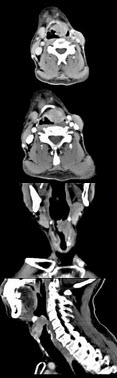

男,53岁,咽部不适半年余,近2个月感咽部疼痛,声嘶,CT如图所示,应诊断为()

A、乳头状瘤

B、喉癌

C、梨状窝癌

D、喉肉芽肿

E、喉部纤维瘤

B